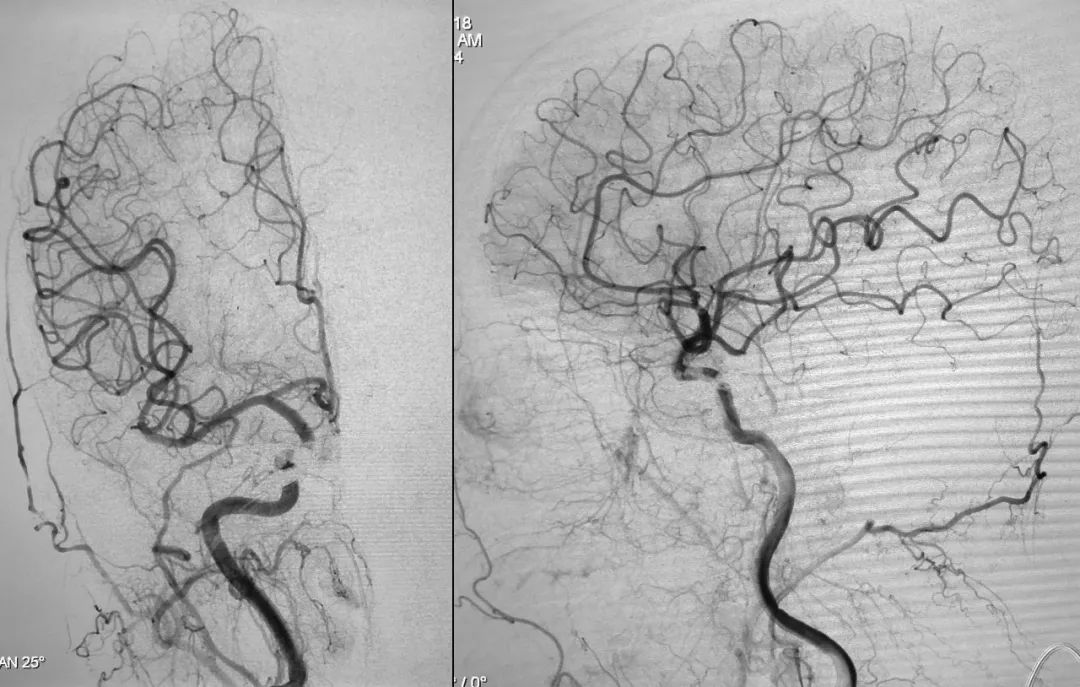

⑧ 术后左侧颈总动脉造影显示瘘口不显影:

将造影管移入右侧颈总动脉,正、侧位造影显示瘘口不显影:

正、侧位蒙片显示Onyx-18胶在右侧海绵窦内的铸型(约4.5 mm):